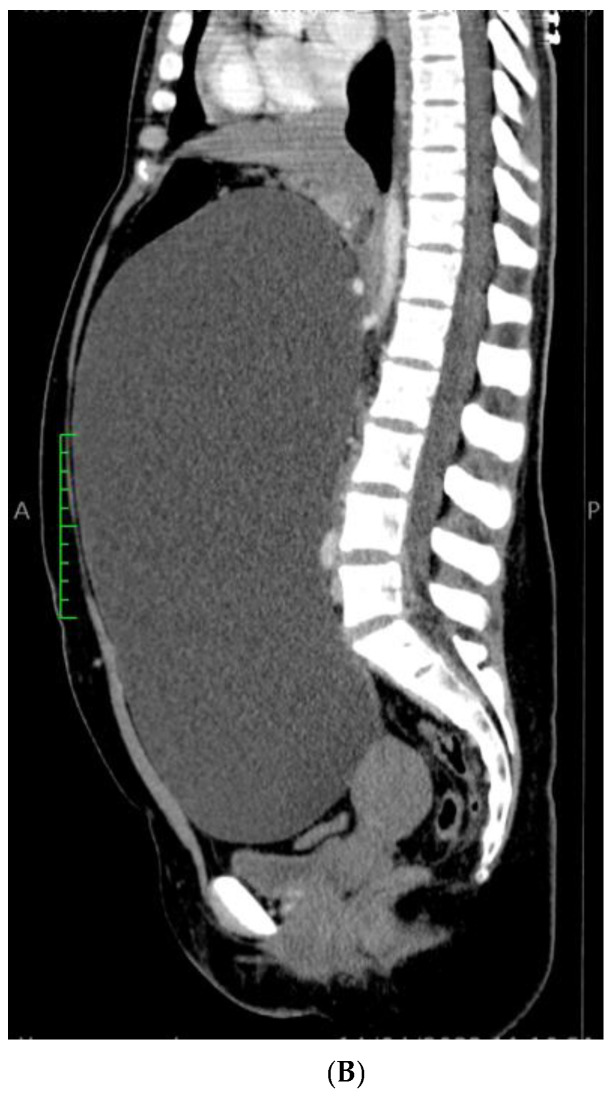

背景及临床意义:输卵管旁囊肿是一种特殊类型的附件囊肿,起源于位于输卵管和卵巢之间的阔韧带间皮,约占附件肿块的10%。有趣的是,大多数输卵管旁囊肿病例最初被误认为卵巢囊肿,每15名患者中只有1名在手术前被怀疑。病例介绍:我们报告了一例21岁女性的巨大输卵管旁囊肿,并附有一些代表性图像和文献综述。囊肿的治疗方法是手术切除附件,最终的术后组织病理学诊断为良性输卵管旁囊肿。结论:本病例强调需要包括输卵管旁囊肿在鉴别诊断盆腔肿块,特别是育龄妇女。据我们所知,这是迄今为止文献报道的最大的输卵管旁囊肿,基于总体尺寸和最高记录的抽吸液量,通过腹腔镜成功处理。本病例另一个值得注意的方面是巨大的输卵管旁囊肿与卵巢粘液囊腺瘤共存。

Background and Clinical Significance: A paratubal cyst, which makes up about 10% of all adnexal masses, is a specific type of adnexal cyst that develops from the mesothelium in the broad ligament located between the fallopian tube and the ovary. Interestingly, the majority of paratubal cyst cases are initially misidentified as ovarian cysts, with suspicion arising in only 1 out of every 15 patients before undergoing surgery. Case Presentation: We report a case of a giant paratubal cyst mimicking an ovarian cyst in a 21-year-old woman supported by some representative images along with a literature review. The cyst's therapeutic management was surgical removal of the adnexa and the final postoperative histopathological diagnosis was that of a benign paratubal cyst. Conclusions: This case highlights the need to include a paratubal cyst in the differential diagnosis of pelvic masses, especially in women of reproductive age. To the best of our knowledge, this represents the largest paratubal cyst reported in the literature to date, based on overall dimensions and the highest recorded volume of aspirated fluid, successfully managed via laparoscopy. A further notable aspect of this case is the coexistence of the giant paratubal cyst with an ovarian mucinous cystadenoma.